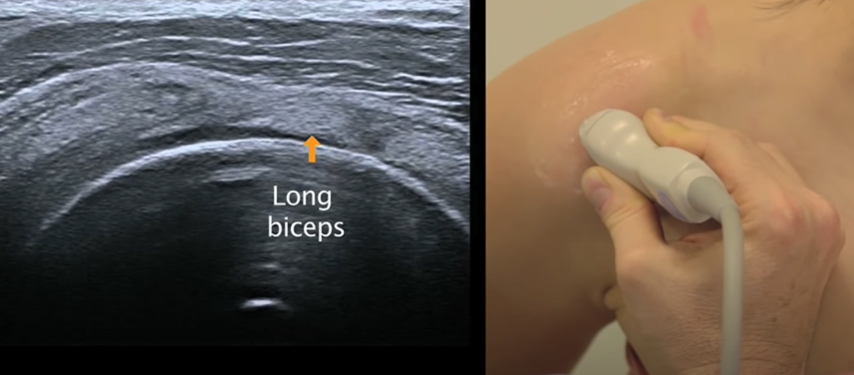

Supra-épineux

- Mains sur les fesses puis adduction (dégage en avant le tubercule majeur qui est sous l’acromion en neutre)

- S’insère sur le tubercule majeur (face horizontale)

- coupe longitidunale (sonde oblique vers le haut et le dedans) avec les fibres du deltodie parralèle au tendon

- coupe axiale (le supra-épineux occuple l’insertion de la surface horizontale, l’infra-épineux la surface oblique du tubercule majeur)

Coupe longitudinale avec fibres parallelles du deltoide

Coupe axiale